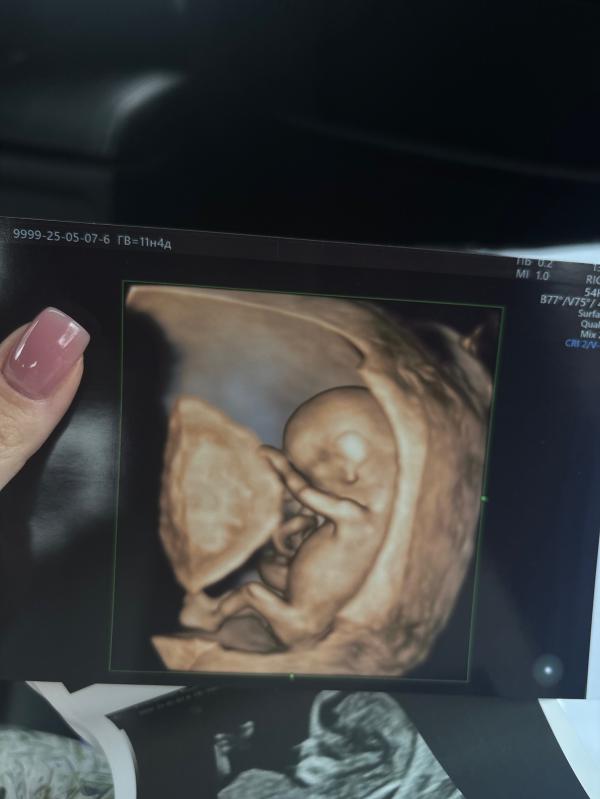

Делюсь своим опытом прохождения первого скрининга в Медике на Тореза.

Врач Тен Наталья Алексеевна

Стоимость 6000₽ УЗИ + 3300₽ кровь

Кровь я сдала за неделю до узи, чтобы сразу получить на руки заключение.

УЗИ делала на сроке 11н4д. КТР 5 см

Всё прекрасно удалось рассмотреть: носик, ушки, мозг, сердечко, ручки, ножки, пальчики — всё было видно!

Врач смотрела очень внимательно, на все мои вопросы отвечала. Обстановка в кабинете спокойная, приятная, я чувствовала себя комфортно.